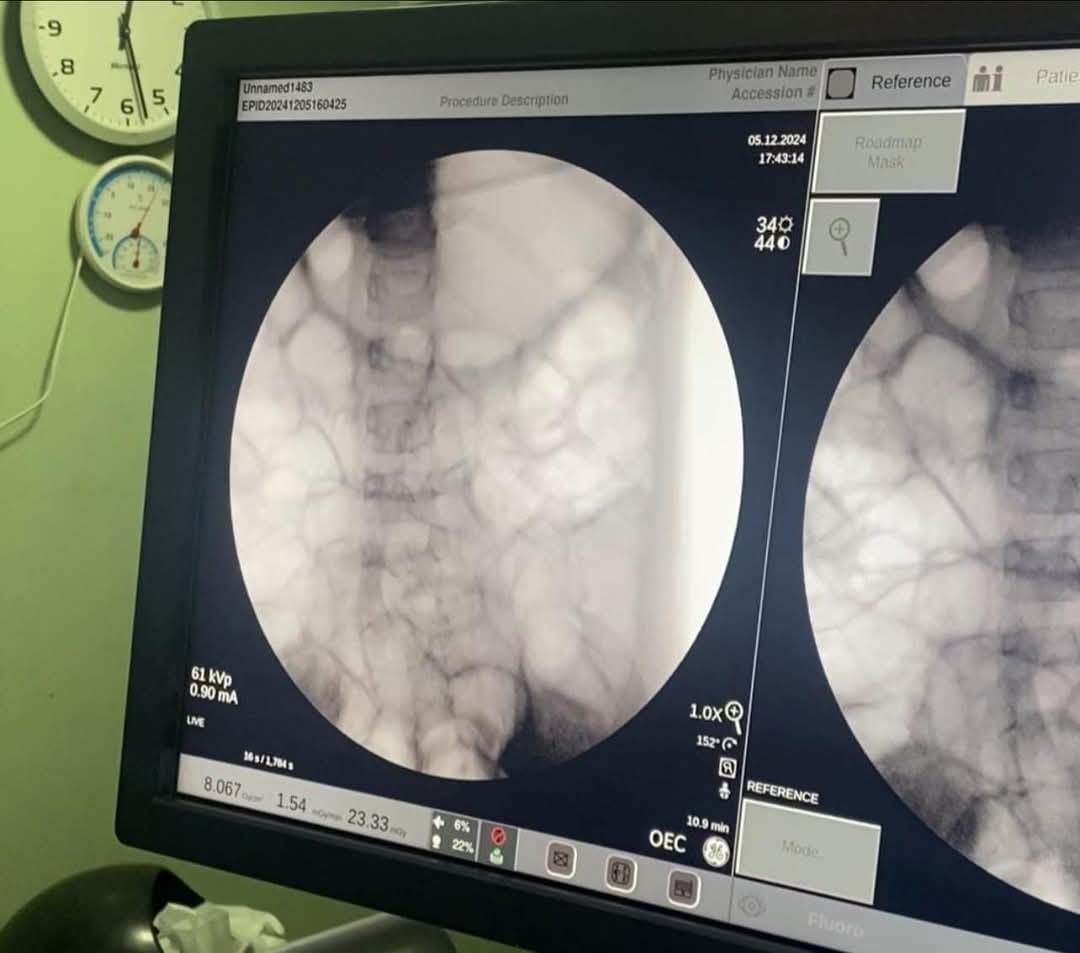

وعلى الفور أدخلت الطفلة إلى غرفة العمليات، حيث تم استخراج قطعة معدنية حادة من براية قلم رصاص كانت مغروسة في جدار المعدة، باستخدام منظار الجهاز الهضمي.